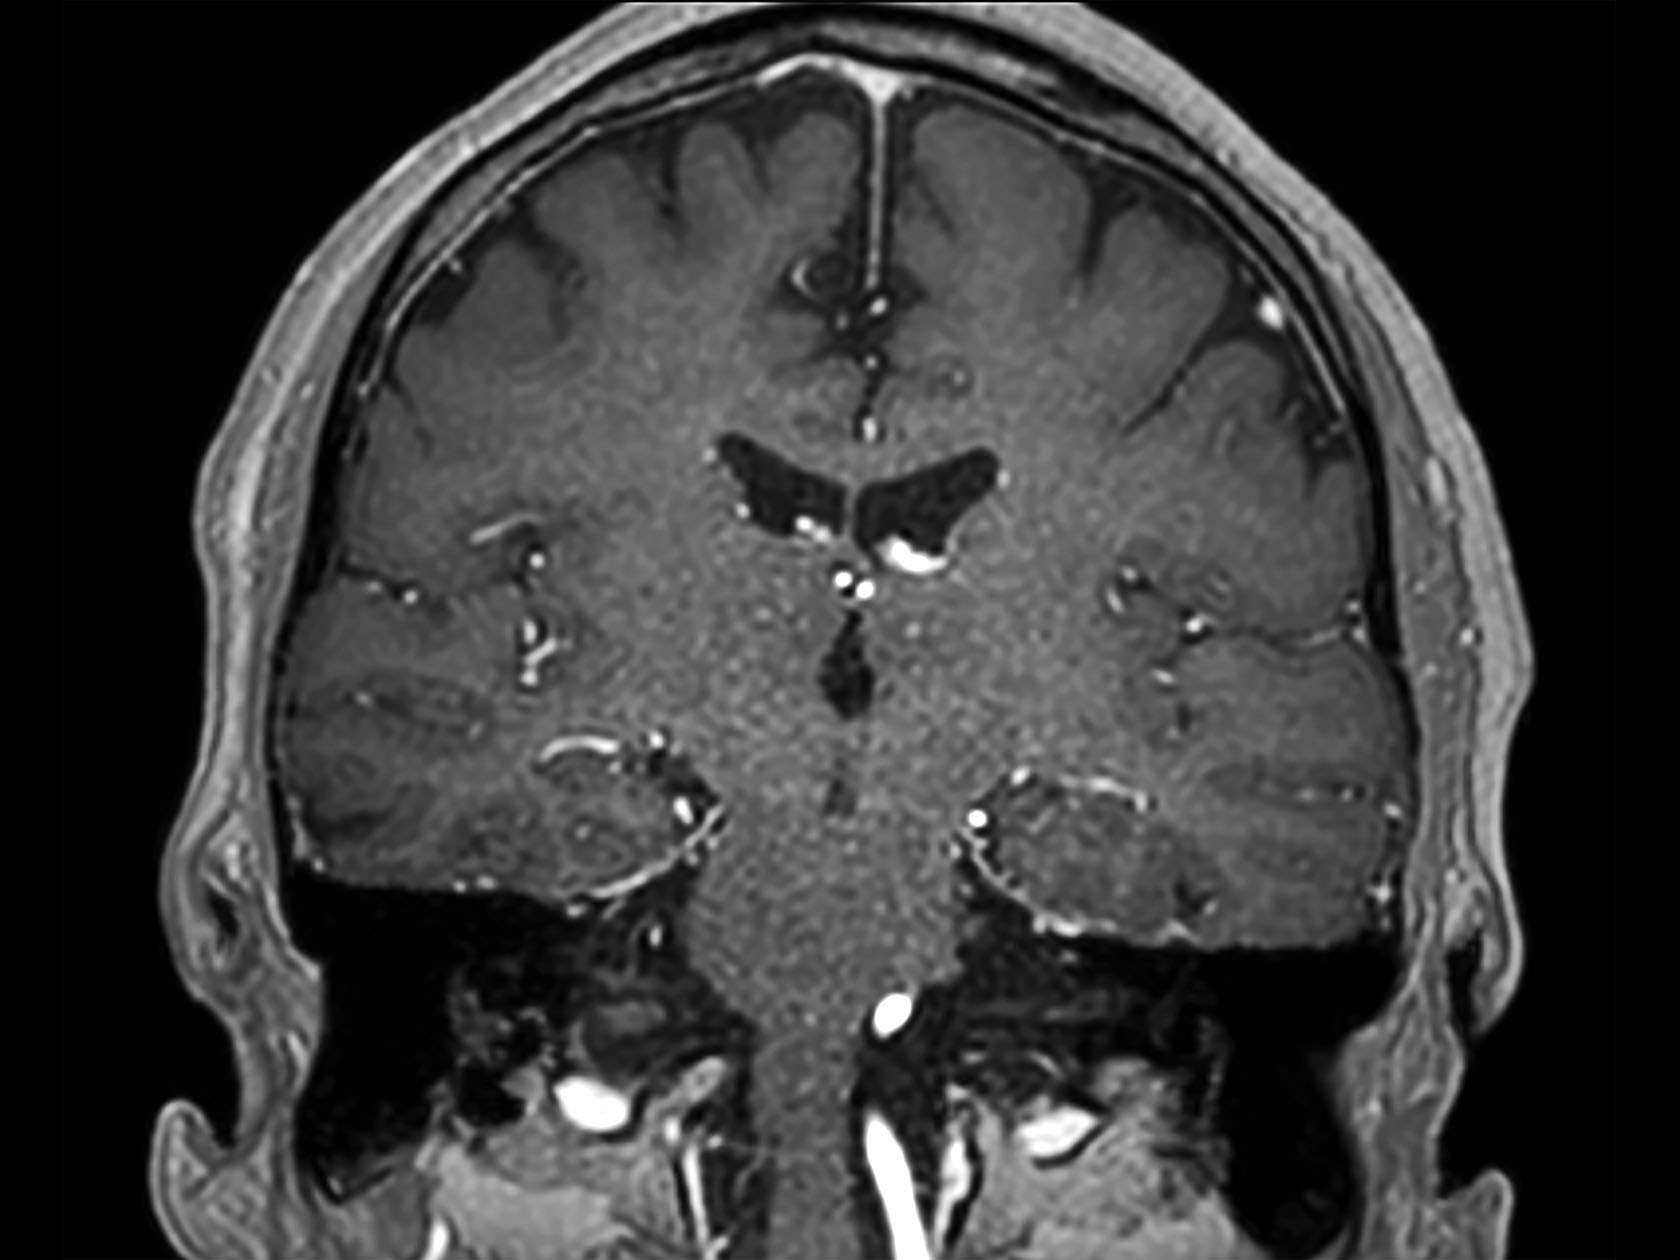

Coronal 3D T1w TFE (post-gado)

Coronal T1w FFE (post-gado)